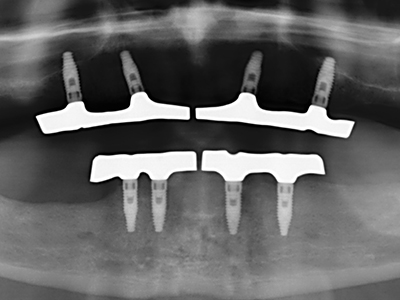

Wie sich in der Vergangenheit gezeigt hat stellt prinzipiell jeder knochenchirurgische Eingriff eine mögliche Indikation für die Piezochirurgie dar. So lässt sich die Präparation des mobilen Segmentes bei der Distraktionsosteogenese (Abb. 23-25) und der Sandwichosteotomie mit speziellen Ansätzen bewerkstelligen, ohne die für den Erfolg beider Techniken essenzielle Blutversorgung des krestalen Anteils zu gefährden (Gonzalez-Garcia, Diniz-Freitas et al. 2008).

Für die Entnahme von Implantaten ist die Präparation eines vestibulären Knochendeckels möglich, der nach Entfernung der Implantatschraube refixiert wird und auf diesem Wege die Kontur des Alveolarfortsatzes erhält.